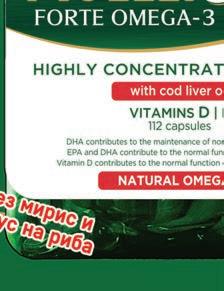

Омега-3